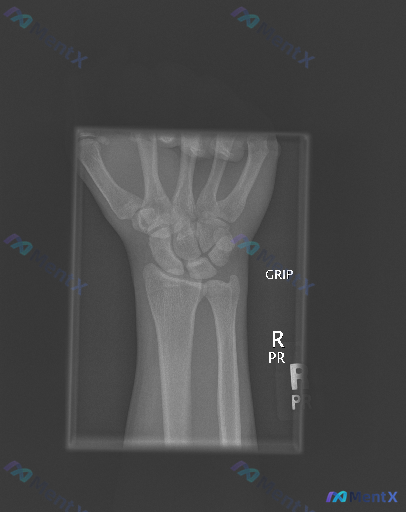

整理到一组右侧腕关节的影像与评估: - 影像:右侧腕关节侧位X光片 - 影像描述:投照体位基本标准,曝光适中;腕骨排列连续,月骨头状骨轴线对齐,未见明显骨折线、皮质中断或脱位;骨质密度均匀,无明显骨质疏松或破坏;桡腕、腕中关节间隙清晰;软组织影轮廓清晰,未见明显肿胀或脂肪垫移位;未见游离骨块、异物或...

腕关节侧位X光片未见明确骨性异常,如果有症状,下一步判断重心该放哪?

整理到一则腕关节侧位X光片的影像观察资料,客观描述如下: - 骨骼方面:桡骨远端背侧、掌侧皮质轮廓清晰,未见明显皮质中断或台阶征;尺骨茎突及可见腕骨皮质连续;未见明显透亮骨折线、皮质裂纹、塌陷或骨小梁紊乱。 - 关节对位:腕骨排列符合生理曲线,未见明显月骨脱位/半脱位;头状骨轴线与桡骨长轴基本对齐;...